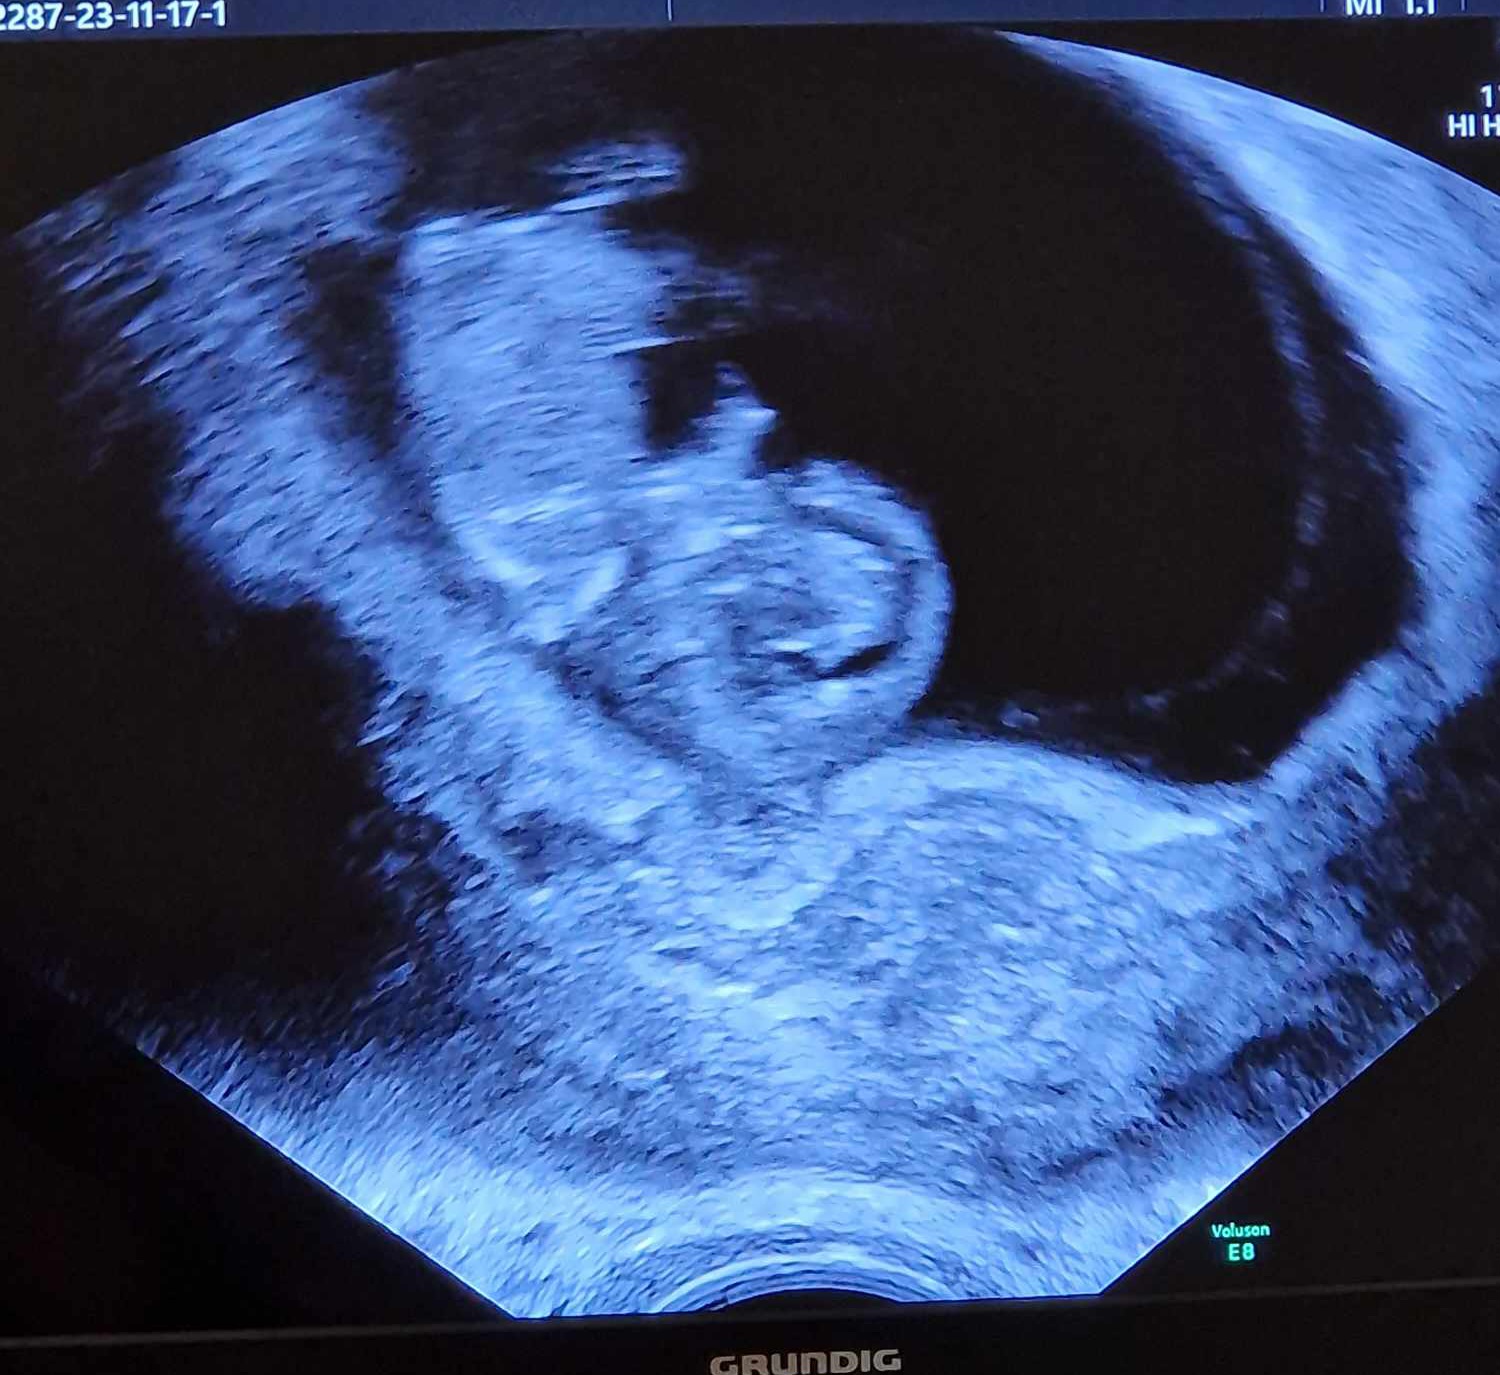

Idag var vi på ultralyd og alt så bra ut :sad010 :Heartred Det lille hjertet slo og bebisen hadde fine bevegelser!

Jeg ble målt til 10+0 men legen mente det kunne hende den var lengre, siden den lå sammenkrøket. Men det stemmer ganske bra med når jeg mener jeg hadde eggløsning, så jeg er fornøyd med det!

Det bittelille mennesket var over 3 cm og hadde allerede armer og bein, noe som for meg her helt utrolig! Jeg er så lettet over at alt så bra ut, i kveld forteller vi nyheten til barna og i morgen får svigers vite det. Så håper vi alt ser bra ut på otul også, om 18 dager.